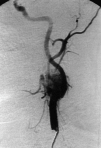

Fig. 2. Imagen angiográfica correspondiente al paraganglioma carotídeo izquierdo. Se observa una masa vascularizada que produce un ensanchamiento de la bifurcación carotídea.